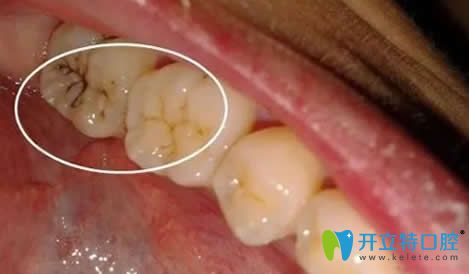

窩溝封閉前的牙齒